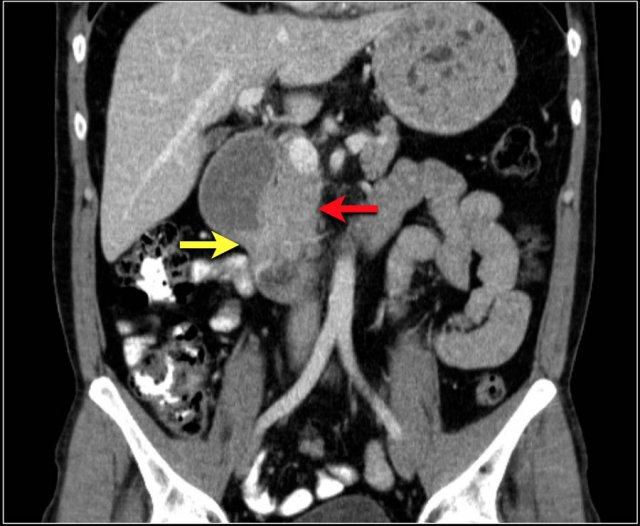

Các hình ảnh cho thấy u carcinoid biểu hiện là một khối tăng sinh mạch (mũi tên đỏ) với phản ứng xơ hóa desmoplastic (mũi tên vàng).

Đây là hình ảnh điển hình của u carcinoid biểu hiện là một khối mạc treo lớn với phản ứng xơ hóa desmoplastic và co kéo các quai ruột non lân cận kèm dày thành ruột (các mũi tên).

U carcinoid có vôi hóa và phản ứng xơ hóa desmoplastic. Tắc ruột non do thành phần trong lòng ruột của u carcinoid. Lưu ý tổn thương di căn gan nhỏ (mũi tên).